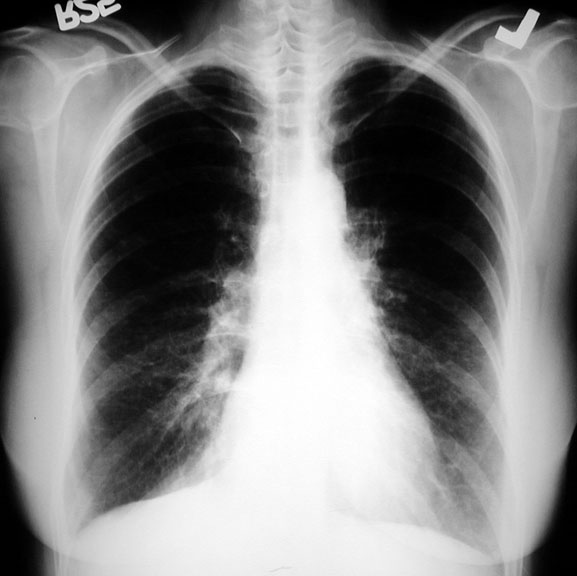

Scleroderma